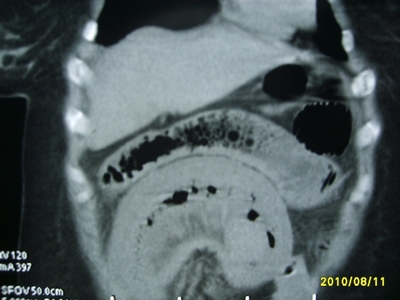

5天前突发腹痛剧烈难忍,伴解淡血水样便。近一天来腹痛缓解,没有明显的腹膜炎的体征。今天照的腹部ct。从ct上看感觉是一个绞窄性肠梗阻,但是现在没有腹痛。不好解释

要有麻烦了,感觉小肠有套叠还有扭转改变,估计部分已有坏死。

高位肠梗阻(不全性),原因小肠(空肠)扭转,肠壁水肿增厚,成年人肠梗阻要排除合并占位,建议手术。

绞窄性肠梗阻_肠管套叠 扭转,肠壁明显水肿。

支持绞窄性肠梗阻,肠壁明显水肿并见有多发小泡状积气--肠坏死

考虑绞窄性肠梗阻并肠坏死。